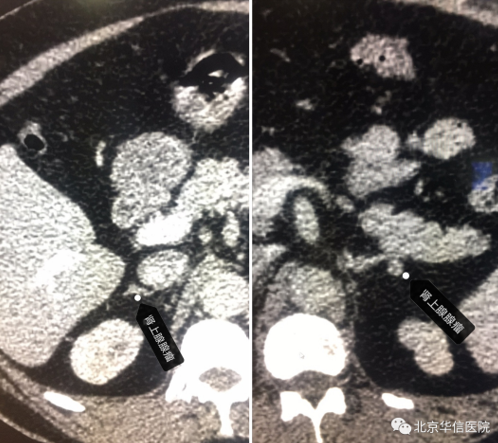

近日,一位中年男性到北京华信医院(清华大学第一附属医院)健康管理中心进行健康体检,测量血压明显升高,医务人员仔细询问后得知男子有高血压病史,平素服用降压药治疗,但降压效果欠佳。尽管患者否认除高血压外的其它病史,但我们观察到患者有“满月脸、水牛背”的体征,是典型的向心性肥胖表现,考虑血压升高背后可能隐藏着“秘密”,其血压升高的原因有可能为继发性,建议做进一步检查以明确诊断。CT结果显示“双侧肾上腺多发结节,考虑腺瘤可能”,化验血液皮质醇水平增高。

这位患者就是因肾上腺肿瘤导致糖皮质激素(主要是皮质醇)分泌过多所致的高血压,又称“库欣综合征”,有多种类型,包括库欣病、异位ACTH综合症、肾上腺肿瘤等。典型病例表现为向心性肥胖、满月脸、多血质、皮肤紫纹等,重型表现为体重减轻、高血压、水肿、低钾性碱中毒,可并发心力衰竭、病理性骨折、脑卒中、肺部感染等。一般依据临床症状或血液糖皮质激素分泌异常可诊断,治疗上依据不同的病因进行相应治疗,如垂体、肾上腺肿瘤等可经手术治疗,一般病情在数月后逐渐好转。